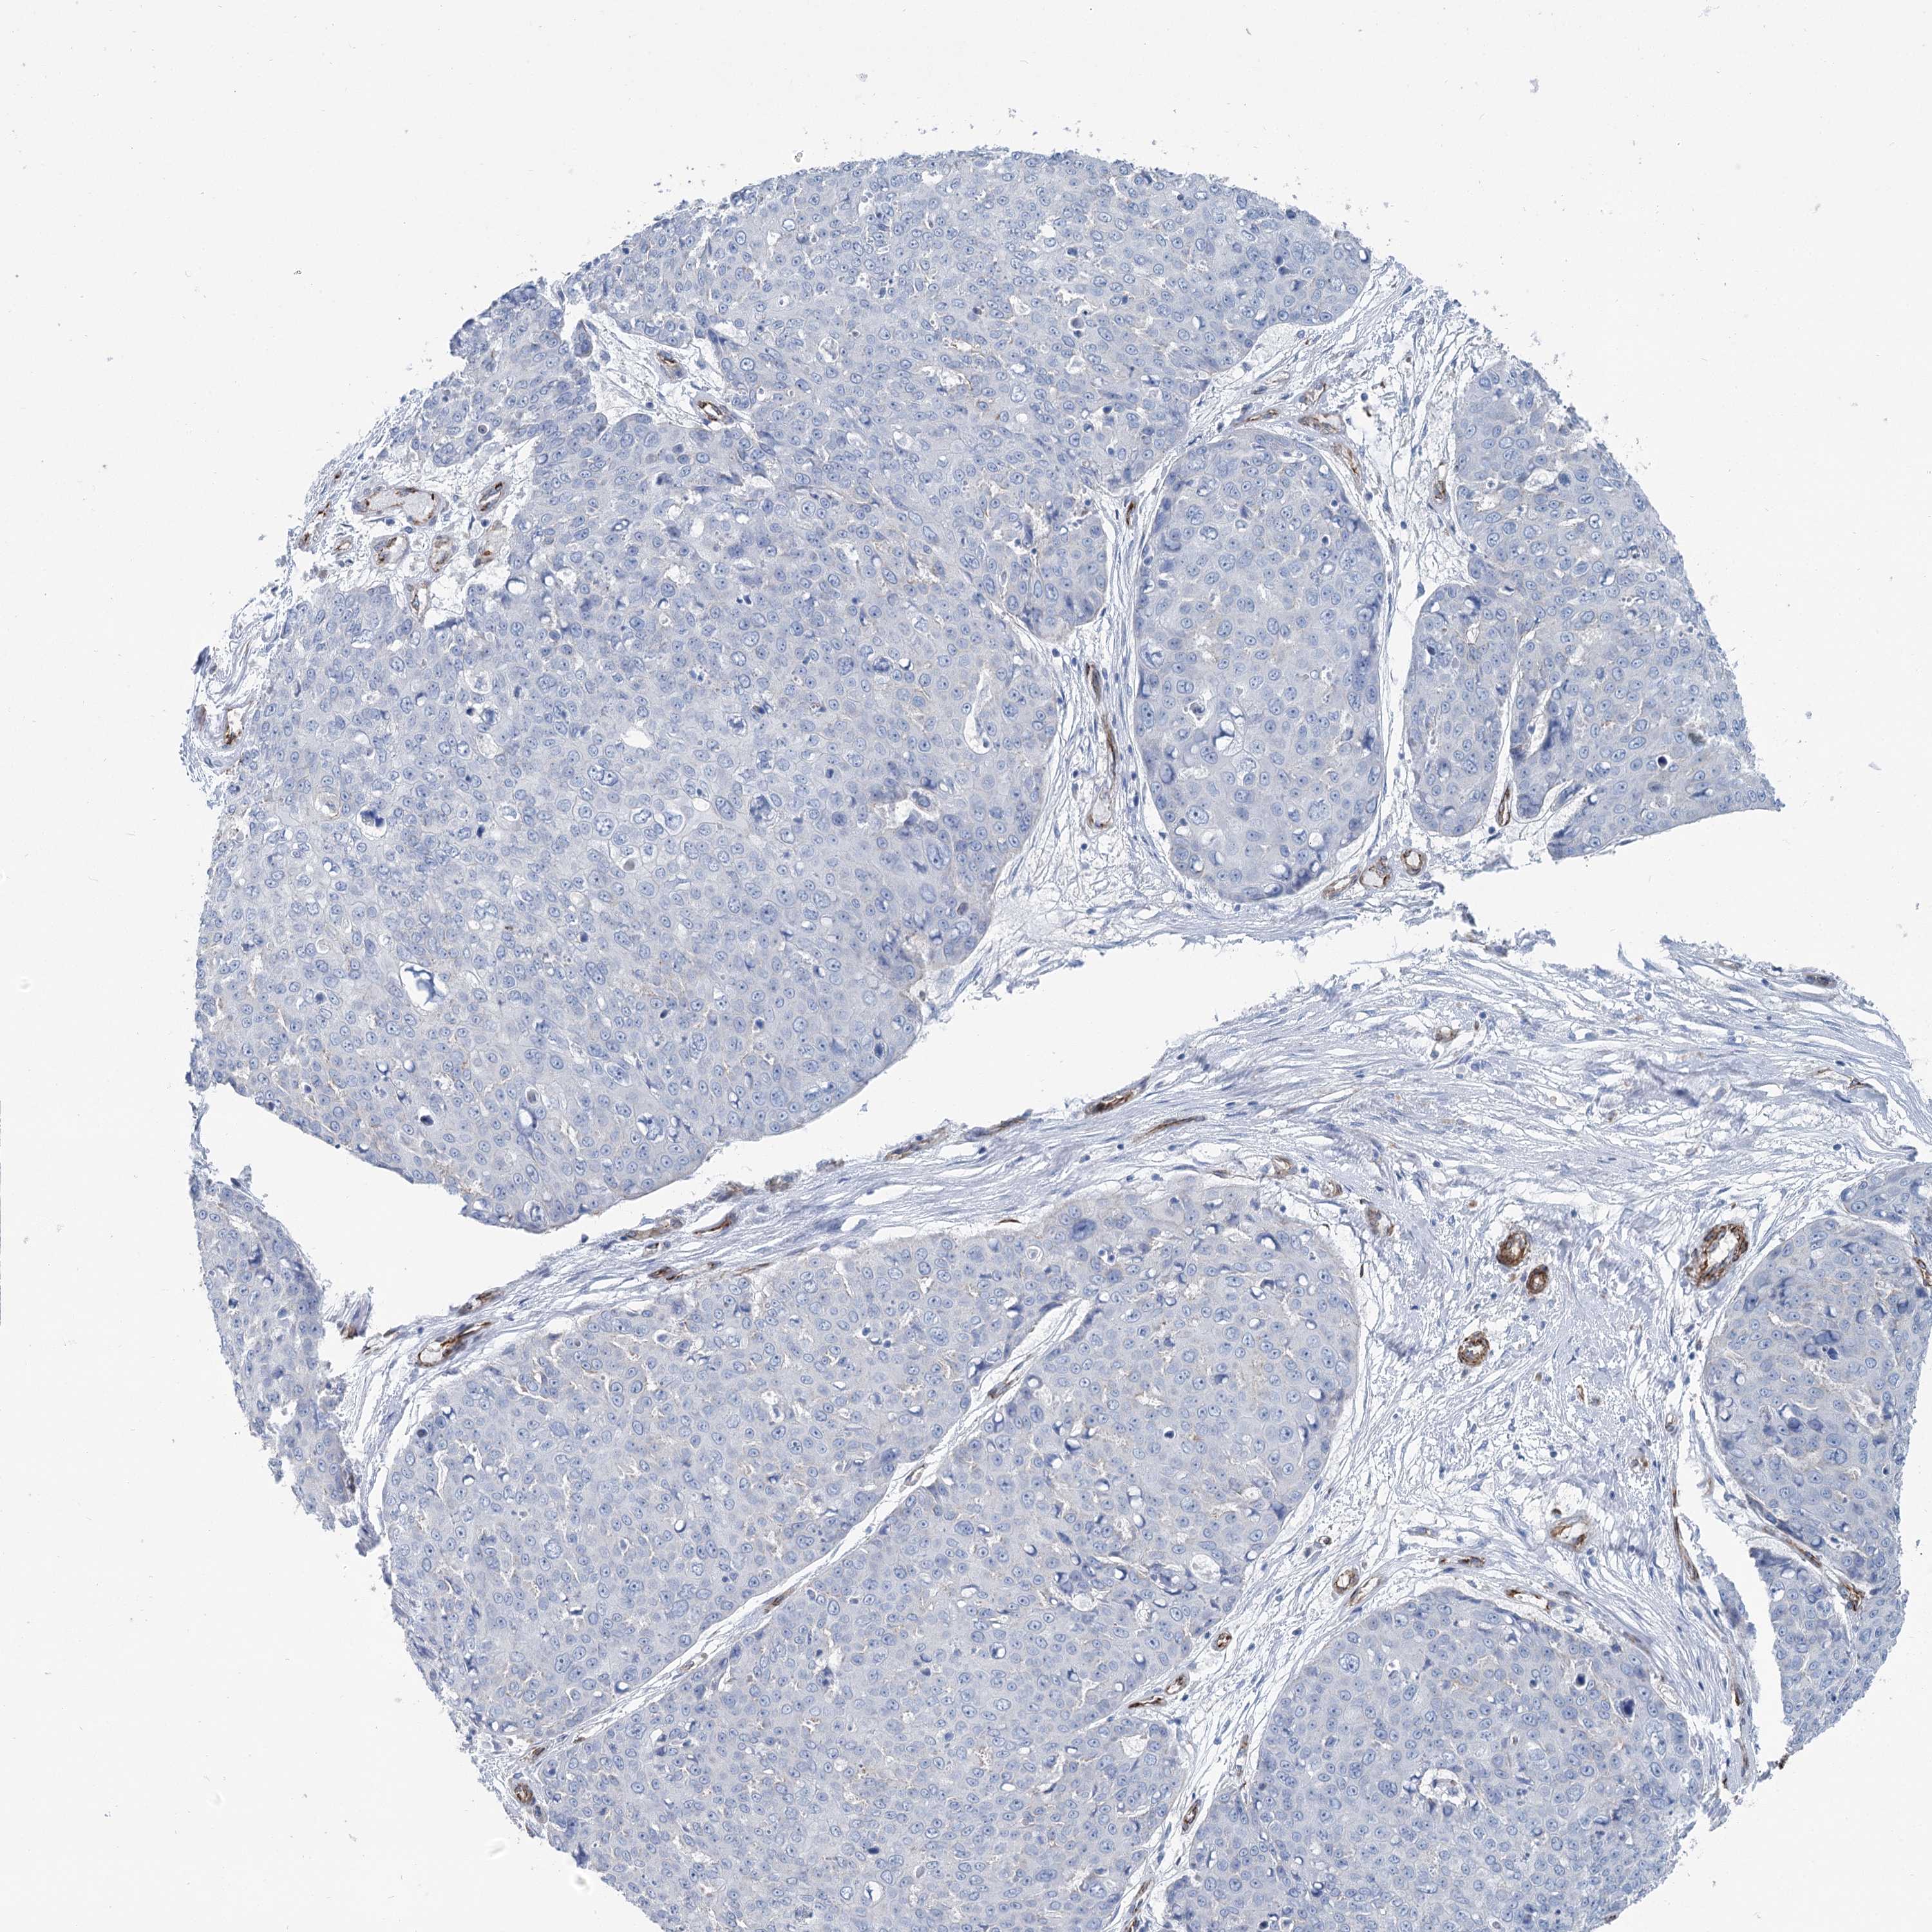

SKIN CANCER - Protein expressioni

A mouse-over function shows sample information and annotation data. Click on an image to view it in a full screen mode. Samples can be filtered based on level of antibody staining by selecting one or several of the following categories: high, medium, low and not detected. The assay and annotation is described here.

Antibody stainingi

Antibody staining in the annotated cell types in the current human tissue is reported as not detected, low, medium, or high, based on conventional immunohistochemistry profiling in selected tissues. This score is based on the combination of the staining intensity and fraction of stained cells.

Each image is clickable and will lead to virtual microscopy that enables deeper exploration of all samples and also displays staining intensity scores, fraction scores and subcellular localization as well as patient and tissue information for each sample.

Antibody HPA038143

Antibody HPA038144

Basal cell carcinoma

Squamous cell carcinoma, NOS

Squamous cell carcinoma, metastatic, NOS